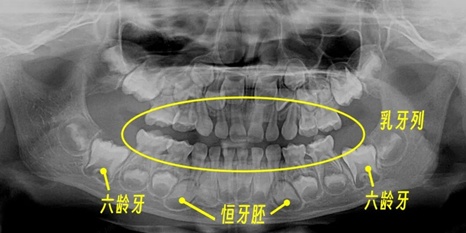

先天缺牙的诊断本身并不复杂。CBCT影像下,牙胚缺失一目了然。真正的挑战在于:如何在颌骨持续发育的背景下,制定一套能够伴随患者成长的修复方案。

小文(化名)的特殊性在于:15岁时口内仅存2颗恒牙(编号15、25),其余均为乳牙。乳牙的牙根结构本就不同于恒牙——更细、更短、固位力更弱。当咬合空间因长期磨损严重不足时,传统冠修复几乎无从下手。

第一,咬合空间不足。乳牙磨耗导致垂直距离降低,上下牙列失去正常咬合关系;第二,乳牙牙体薄弱。牙根纤细意味着修复体难以获得有效固位;第三,颌骨发育期限制。未成年患者不宜进行永久性修复;第四,牙槽骨骨量不足。缺乏恒牙胚刺激的区域,骨密度普遍偏低。